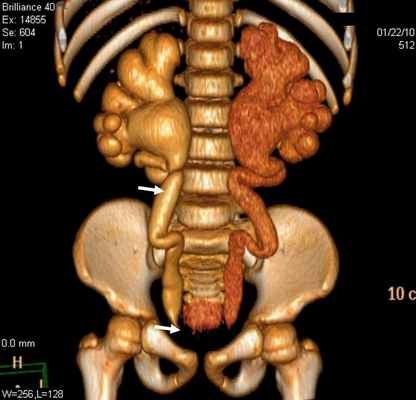

Болюсное введение контрастного вещества и последующее динамическое исследование различных фаз контрастирования способствует четкому выявлению уретероцеле (рис. 3б).

Уретероцеле обнаружено у 3 (8,1%) пациентов из 37. Этот порок уретеровезикального сегмента на МСКТ характеризовался с кистовидным расширением внутрипузырного сегмента мочеточника. При этом отчетливо определяется округлая полость, вдающаяся в просвет мочевого пузыря (рис. 3).

Хотя по литературным данным эктопия устьев мочеточника наблюдается чаще, чем другие варианты пороков данной области, но нами были диагностированы у 5 (13,5%) пациентов. Эктопия устьев мочеточника на МСКТ характеризовался удвоением мочеточника у 3 пациентов и эктопическим расположением устьев мочеточника у всех больных.

Рис 3. МСКТ картина уретероцеле. Трехмерная реконструкция. Удвоение почек и мочеточника справа (a) и уретероцеле слева (б)

Во всех наблюдениях устья мочеточников открывались в мочевой пузырь. В отличие от экскреторной урографии на МСКТ четко определяются изменения со стороны почек и мочеточника, особенно при трехмерной реконструкции.

Стеноз устья мочеточника на МСКТ выявлен в 29 (78,4%) наблюдениях (рис 4). Данная патология у 17 детей была с обеих сторон, а 3 наблюдениях этот порок сочетался с уретероцеле и эктопией устьев мочеточника.